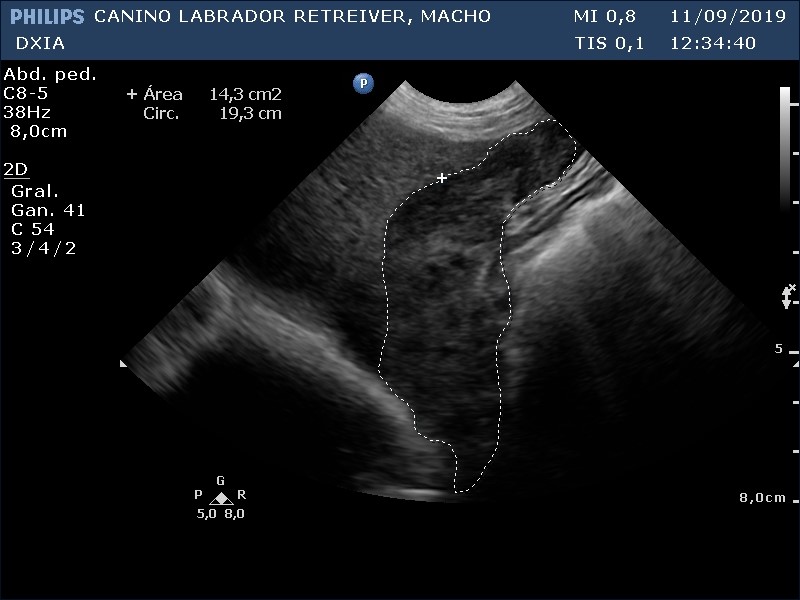

Lóbulo hepático.

Parénquima hepático homogéneo en lóbulos caudal a la vesícula biliar y lóbulo derecho próximo al estómago, pero en el resto del hígado se observa hepatomegalia (al presentar bordes hepáticos redondeados) junto con patrón marcado nodular que le da heterogenicidad. Se realiza PAF ecoguiada para su posterior análisis anatomopatológico, pero si no es suficiente la muestra se requerirá la realización de biopsia.

Vesícula biliar con pared fina e hiperecogénica. No presencia de barro biliar.